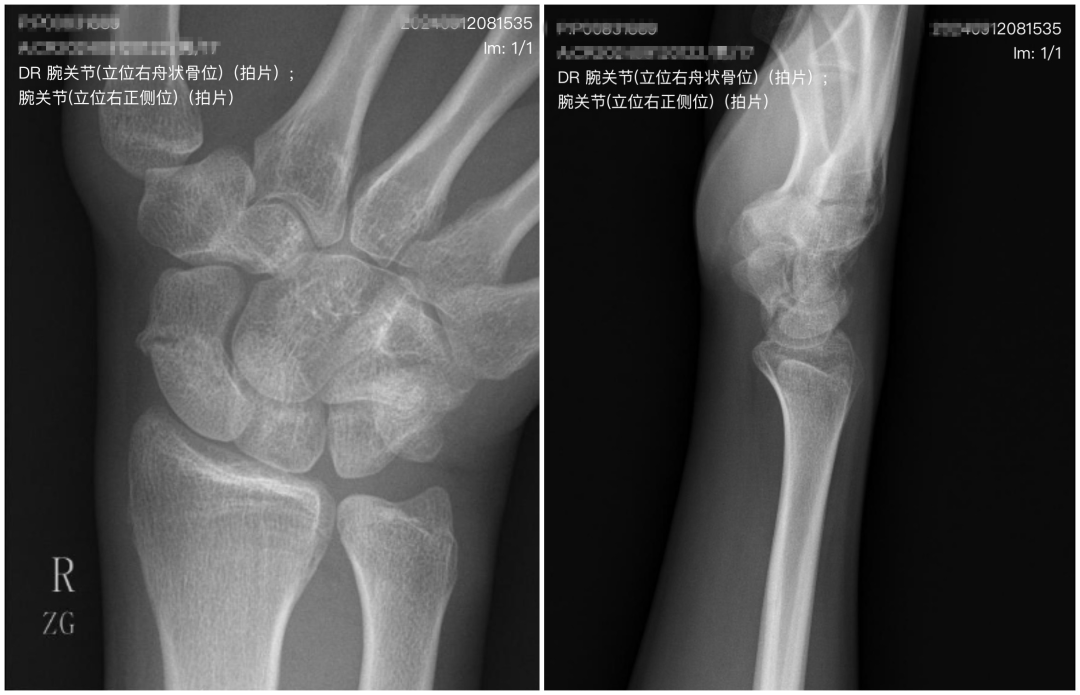

据悉,该患者为青年男性,6个月前摔伤右腕部,局部疼痛、肿胀、活动受限,未引起足够重视,没有进行适当治疗。一周前,再次杵伤右腕部,于当地医院检查,拍片提示右腕舟骨骨不连。

前段时间,该患者到烟台山医院东院手外一科就诊,李晓副主任医师接诊后确定诊断为“右腕舟骨骨不连”,建议患者接受手术治疗。该患者有参军的想法,对术后瘢痕有着极高的要求,希望不要因此影响入伍。付胜强主任医师组织科室医疗团队进行病例讨论,根据病例特点,结合患者需求,拟定了“骨科机器人引导下空心钉精准固定骨折,腕关节镜下磨除硬化骨并自体骨植骨”的手术方案。